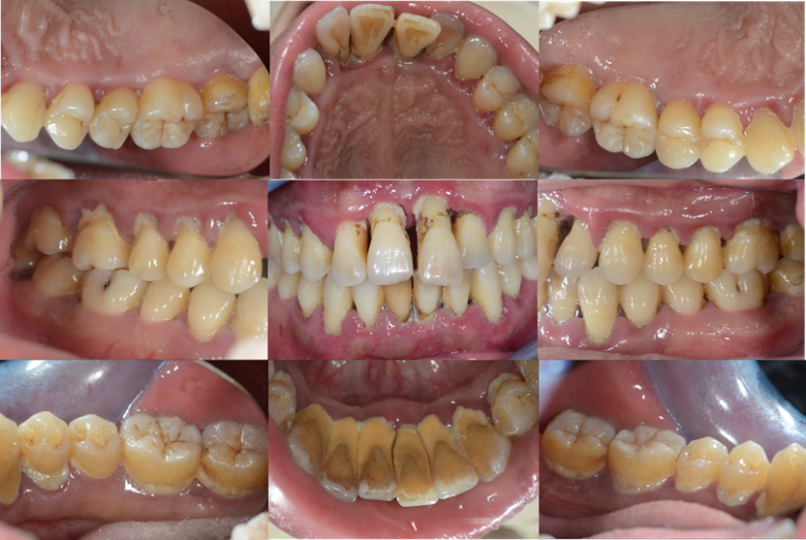

▲牙周治疗前口内彩幻